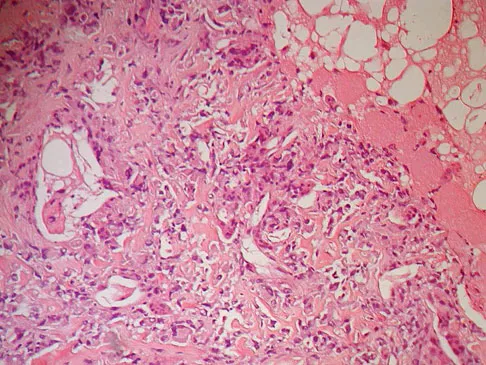

The biopsy specimens seen in Figures 55a and 55b are from a lytic lesion in the sacrum of a 58-year-old man. What is the most likely diagnosis?

Explanation

The lesion is a chordoma and the other listed choices can be eliminated based on the histology. Many tumors can occur in the sacrum including chordoma, multiple myeloma, giant cell tumor, aneurysmal bone cyst, and metastatic disease. The histology in this patient shows a lobulated lesion on low power with fibrous septae separating the lobules. At higher magnification, the cells have eosinophilic vacuolated cytoplasm and are called physaliferous cells. Chordoma is a low-grade neoplasm that most commonly occurs in the sacrum and rarely in the base of the skull. The diagnosis is often delayed. Chordoma is thought to originate from notochordal remnants. Chordoma typically occurs in the midline and has an associated soft-tissue mass. Wold LE, Adler CP, Sim FH, et al: Atlas of Orthopedic Pathology, ed 2. Philadelphia, PA, WB Saunders, 2003, p 372. Fuchs B, Dickey ID, Yaszemski MJ, et al: Operative management of sacral chordoma. J Bone Joint Surg Am 2005;87:2211-2216.